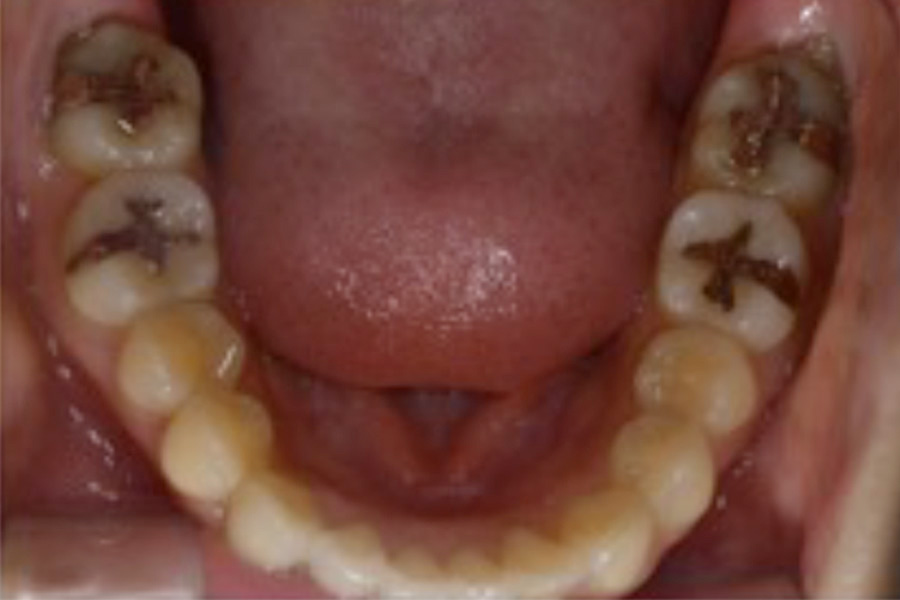

治療前

主訴 右上が気になる。下顎の歯並びを治したい。

治療内容 目立ちにくいマウスピース矯正(非抜歯矯正)

歯と歯の間に隙間をつくることにより、歯列弓を広げながら治療を行いました。